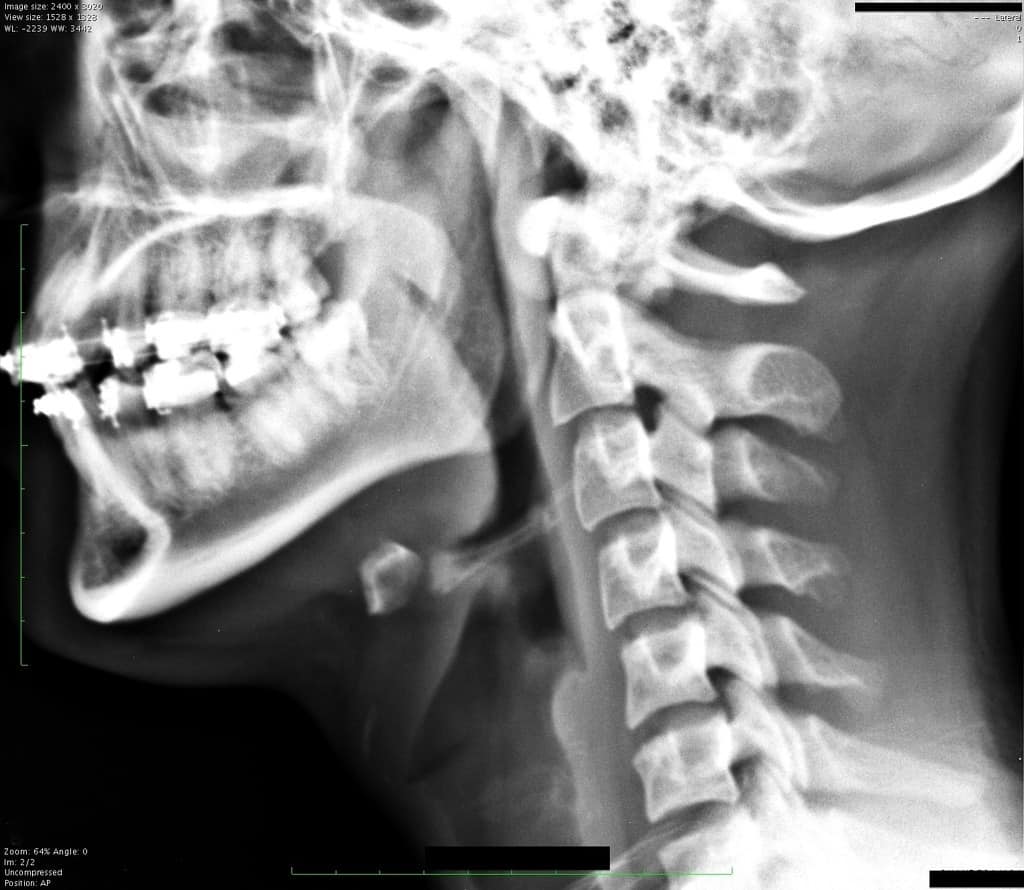

Gãy xương móng

» Thông tin: Nữ giới – 17 tuổi.

» Lâm sàng: Chấn thương vùng cổ.